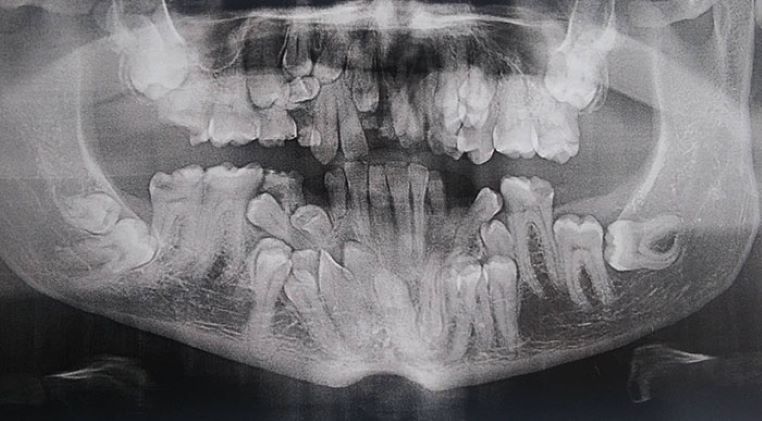

Une radiographie dentaire impressionnante !

galerie-rayon-x-dentiste